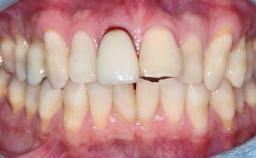

An 80-year-old female patient was referred to clinic for rehabilitation of her dentition. The patient’s medical history revealed no significant findings that would preclude routine dental and oral surgical procedures. She reported no drug allergies and was currently taking no prescription medications.

Her chief complaint was her inability to masticate efficiently due to the recent loss of her mandibular second premolars and first molars bilaterally. She expressed a desire for fixed prostheses in the shortest possible time due to her advanced age, requesting that replacement teeth should look as natural as possible. She was otherwise comfortable and not experiencing any symptoms from her teeth.